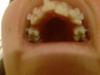

Покажу пару фотографий что у меня сейчас (извиняюсь за качество, фоткаю на мабилу

):

Вот так все ужасно выглядит. Ну ничего, будем лечиться!